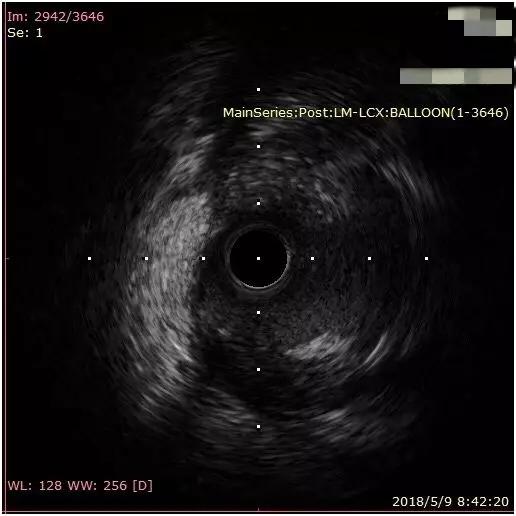

主干分叉病变需要行血管内超声来指导治疗。血管内超声提示回旋支开口斑块负荷重,最小管腔面积尚可。(如图12)

微信图片_20190527095817.jpg图12 回旋支开口

回旋支开口斑块负荷重,最小管腔面积>5mm2。(如图22)

微信图片_20190527095842.jpg图22 血管内超声显示回旋支开口面积5.13mm2